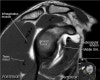

어깨 관절의 MRI 단면영상

- Coronal section

Long head 바깥의 고신호는 Biceps groove의 Normal fluid

Acromion의 하면에 부착하는 저신호 : Deltoid tendon or Corocoacromial ligament일수도 있음

Enthesophyte로 오진가능하나 정상 부착부 소견